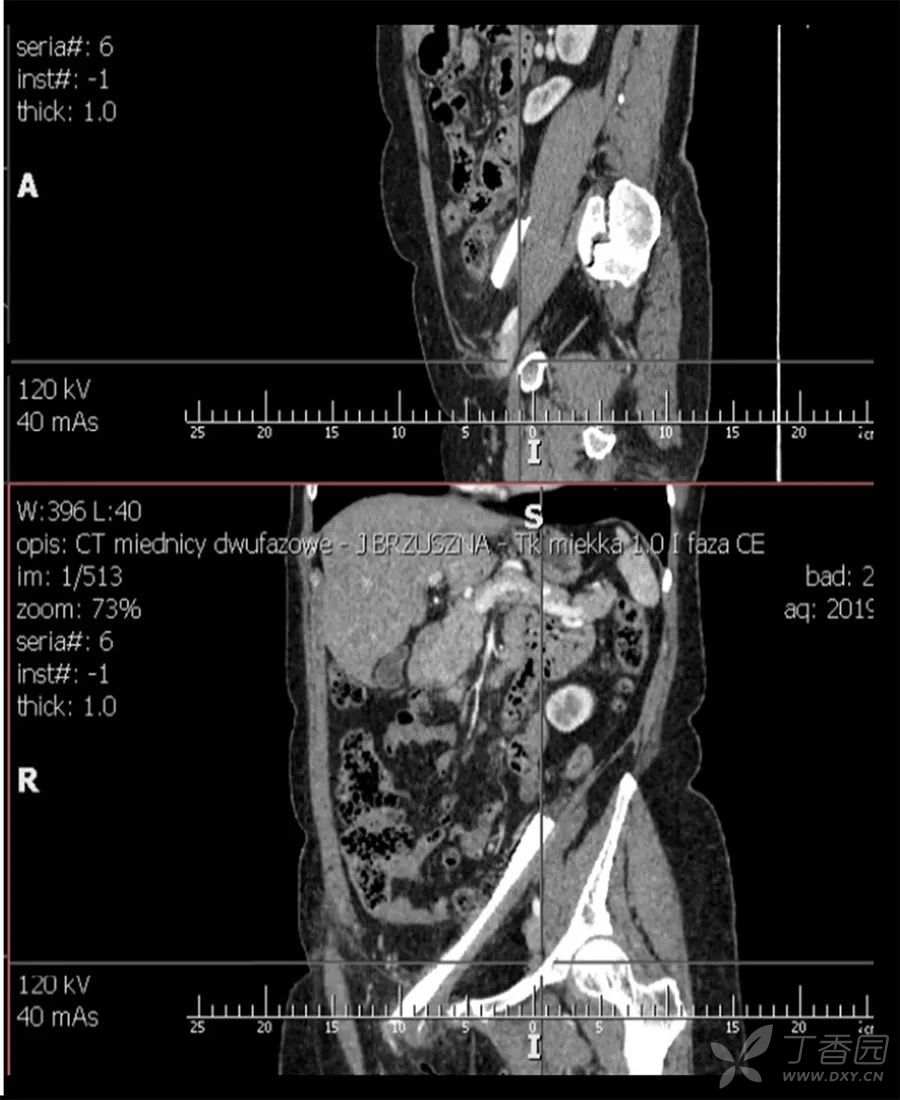

腹腔CT

在腹腔内发现一块19厘米长的玻璃碎片,在盆腔内呈环状。